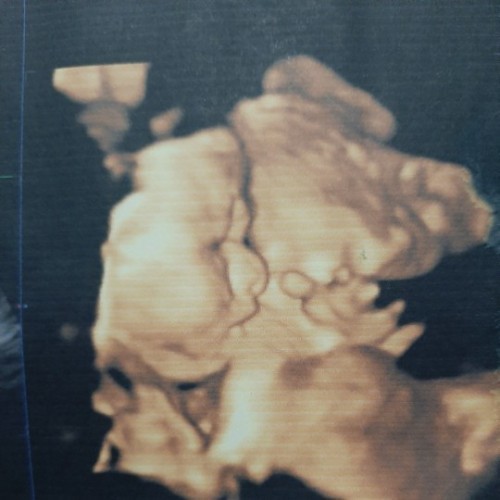

ลูกสาวจ้า กำหนดคลอด 1 พ.ย.

ลูกสาวจ้า เเม่ๆเดือนพฤศจิกายน ได้ลูกสาวหรือลูกชายกันค่ะ💕💕